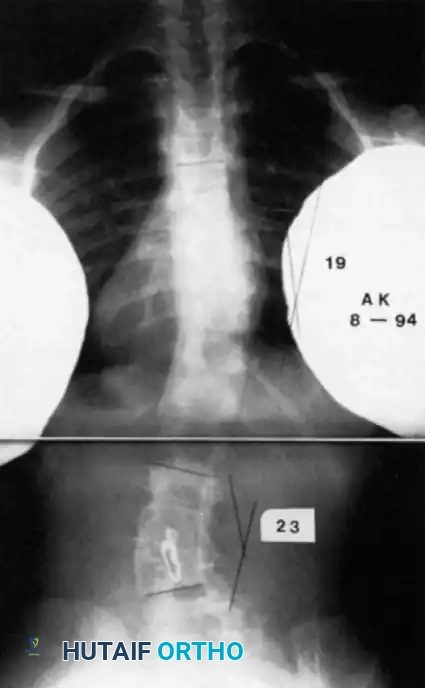

Image

Radiographic examples of progressive congenital curves requiring early intervention.